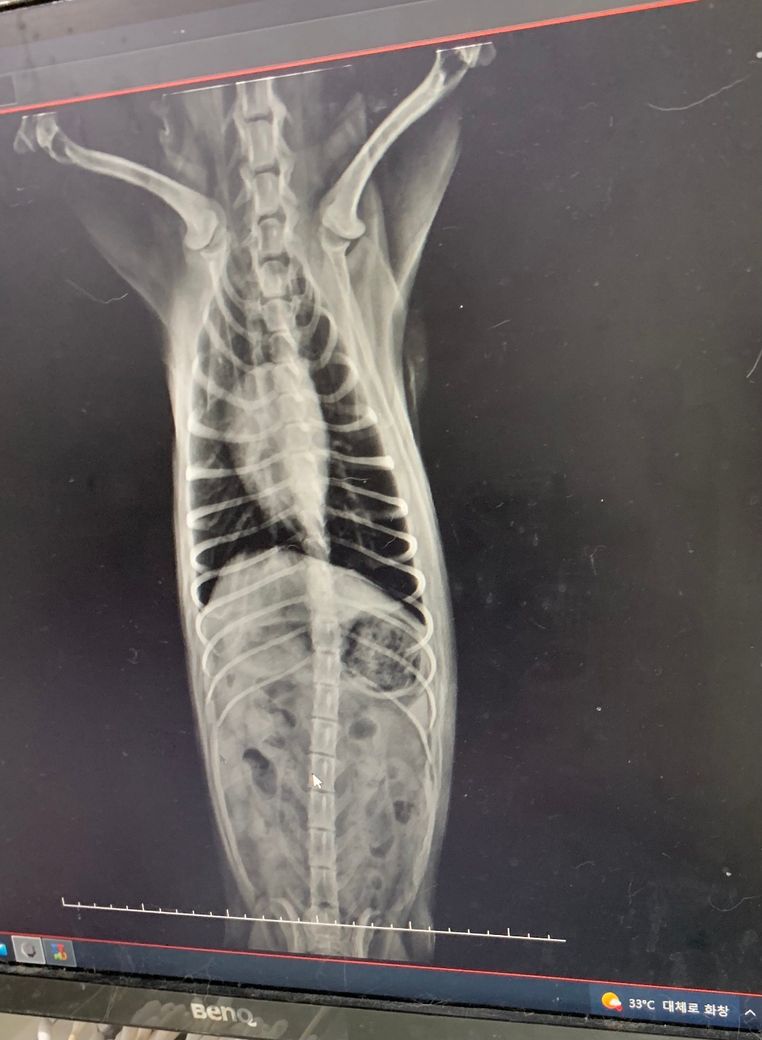

병원에서 간 크기 엑스레이를 찍었는데 간이 작단 말씀이 있으시고 구체적으로 잘 못들어서요 ㅠㅠ

혹시 한번 봐주실 선생님 계시나요?

간크기가 평균 일반 아이들 크기에 비해 많이 작은 편인지 아니면 적당히 작은 편인지 궁급합니다.

정상의 1/2 정도 크기 밖에 안되는지요? 아니면 그보다 더 한가요?

엑스레이로 간의 크기를 평가할때 기준은 위의 사진처럼 빨강색으로 표시된 위내에 있는 가스를 보고 축을 세운 그 기준이

늑골의 축인 노란색과 평행한것을 기준으로 삼습니다.

그래서 이 노란색 축과 평행하면 정상, 노란색 축보다 뒤로 밀려 보이면 간이 커진것, 노란색 축쪼으로 당겨져 보이면 작아진것으로 측정합니다. (많은 방법이 있지만 가장 간단하고 일반적으로 많이 사용하는 방법입니다.)

그것에 비해 첨부하신 사진을 보면

전형적으로 늑간 축쪽으로 위축이 이동한 상태 즉, 소간증 양상을 보이고 있습니다.

품종을 고려하더라도 상당히 감소한것으로 판단됩니다.

간이 다른 개체에 비해 얼마만큼 감소했는지는 CT를 통해 확인하는것이지 방사선 검사를 통해 확인하는것은 아닙니다.

다만 정상인 상태보다 위축의 각도를 고려할때 길이가 1/2 정도로 감소했으니 간크기 즉 용적인 세제곱만큼 감소했다고 가정한다면

1/8로 감소한 상태라고 해석하는게 비공식적으로는 합당한 추정입니다.

심장도 크기가 줄어 있고 흉골에 떠있을만큼 크기가 줄어든 상태인점, 말티푸인점, 4세정도의 중년령인점 등을 고려할때 에디슨병과 같은 내분비계질환이나

콩팥의 크기 증가도 동반되어 관찰되는점을 고려할때 PSS나 MVD 등을 고려해야 하고 간경화의 가능성도 같이 고려되어야 하는 상태로 생각됩니다.